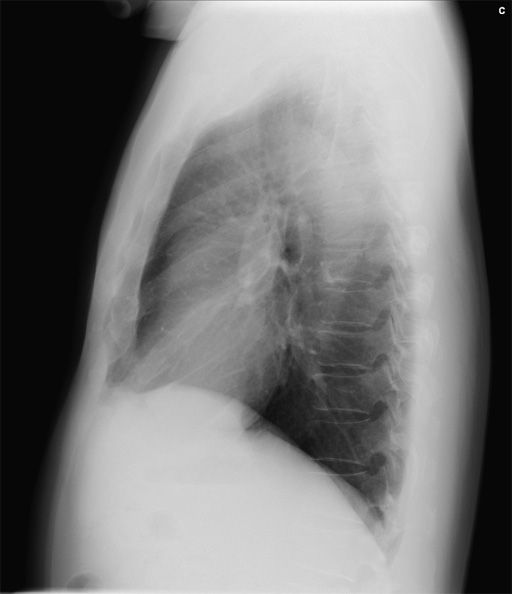

(正面像) 図2 初診時 単純X線写真

図2 初診時 単純X線写真

(側面像) 図3 胸部CT 縦隔条件